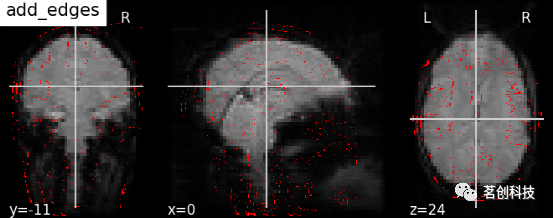

添加边缘,轮廓线,轮廓填充,标记,比例尺

display.add_edges (img):添加图像的边缘。

# 导入图像处理工具进行脑功能图像的基本处理

from nilearn import image

mean_haxby_img = image.mean_img(haxby_func_filename)

display = plotting.plot_anat(mean_haxby_img, title="add_edges")

display.add_edges(haxby_anat_filename, color='r')